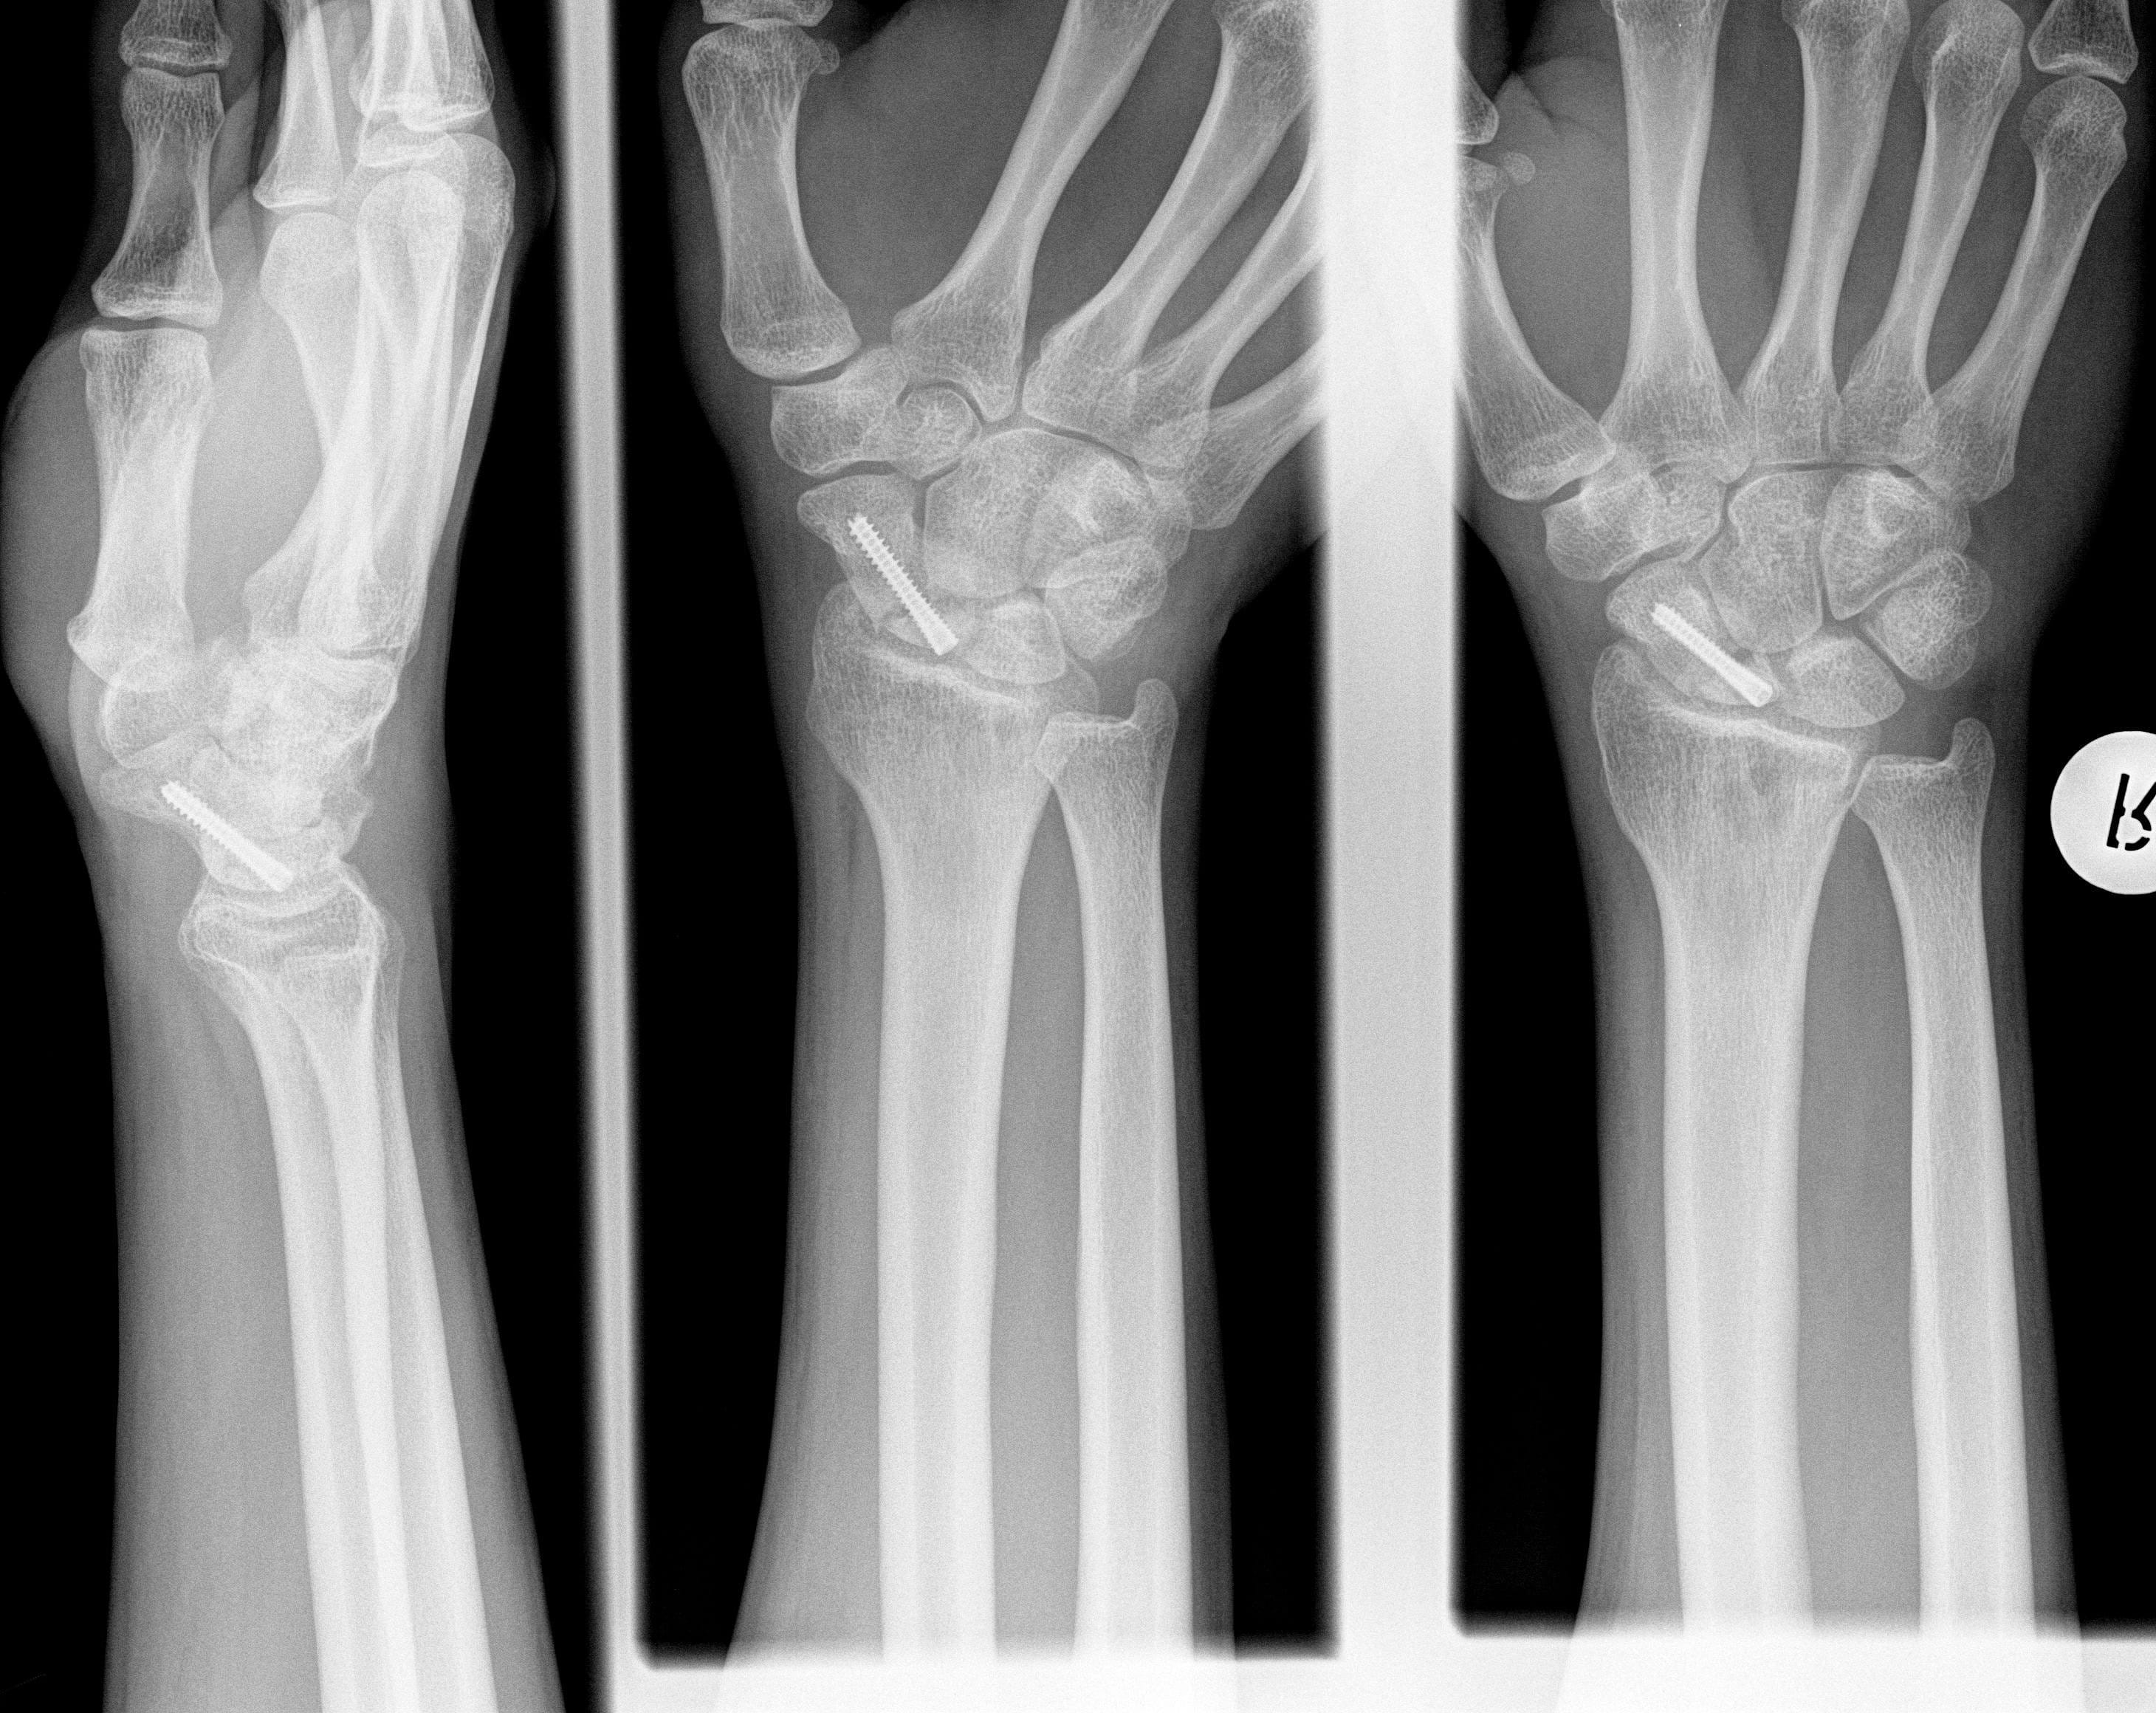

Fotos El esfenoides: Fractura de falange. 2 imágenes 1 caso.

Ver Microosteosíntesis con tornillos a cielo cerrado en las fracturas de la tendencias